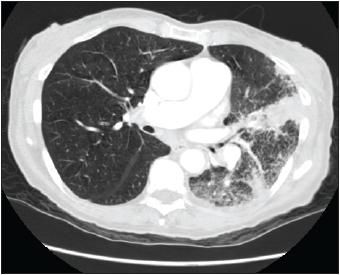

During the initial examination, the patient's temperature was 39.9C (103.9F). Her pulse rate was 104 beats per minute. Blood pressure was 124/74 mm Hg, respiration rate was 24 breaths per minute. Arterial blood gas analysis on admission showed significant hypoxemia (pH was 7.44, PaCO2 was 34 mm Hg, PaO2 was 39 mm Hg, bicarbonate level was 23 mEq/L, and oxygen saturation was 76% on room air). The leukocyte count was 7100/?L, and it increased to 15,200/?L, with 40% bands, in 48 hours. Results of the basic metabolic panel, coagulation profile, and liver function tests were normal. Chest auscultation revealed decreased breath sounds in the left lung base and dullness to percussion in the left midlung. A chest radiograph showed increased density in the left lingular area and a small left pleural effusion (Figure 1). ACT scan of the chest showed a lingular infiltrate with compressive atelectasis and left pleural effusion (Figure 2). A 2-dimensional echocardiogram showed no vegetations. The patient was given moxifloxacin 400 mg IV daily and aztreonam 2 g IV q8h.

Figure 2 -

ACTscan of the chestwith contrastshows a lingularinfiltrate withcompressiveatelectasis andleft pleuraleffusion.